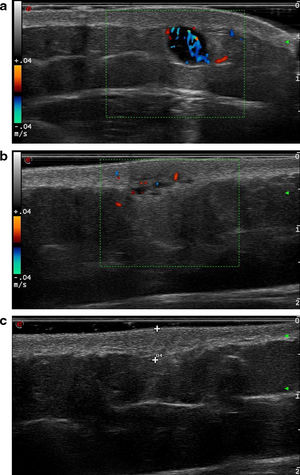

Las ecografías fueron realizadas con una sonda de 18MHz del ecógrafo Esaote Mylab™ ClassC. Los hallazgos se recogen en la tabla 1. Agrupamos las lesiones en tres patrones ecográficos. El patrón nodular (3/10) englobaba lesiones redondeadas, con unos bordes bien definidos e hipoecoicas (fig. 1a). El patrón pseudonodular (6/10) incluía lesiones polilobuladas, de bordes mal definidos y heteroecoicas (fig. 1b). La lesión restante, de un patrón difuso (1/10), era isoecoica, de bordes mal definidos y una morfología difusa (fig. 1c).

a)Ecografía correspondiente a la lesión número2, que muestra una lesión hipoecoica, de morfología redondeada y bordes bien definidos, siguiendo un patrón nodular. Se aprecia además la presencia de refuerzo posterior e importante vascularización. b)Ecografía correspondiente a la lesión número4. En este caso se aprecia una lesión heteroecoica, polilobulada y con bordes mal definidos, característica del patrón pseudonodular. La vascularización está presente, pero es menos profusa que en el caso anterior. c)Ecografía correspondiente a la lesión número10. Se trata de una lesión isoecoica y mal definida que sigue un patrón difuso.